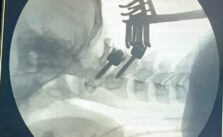

आयुष्मान भारत योजना से रीढ़ की टूटी हड्डी का नि:शुल्क हुआ ऑपरेशन

रीवा 21 जनवरी 2023. आयुष्मान भारत योजना गंभीर रोगों के इलाज